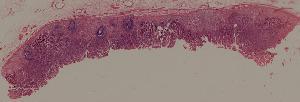

48.病毒性心肌炎

49.梅毒性主动脉炎

50.大叶性肺炎

51.肺肉质变

52.小叶性肺炎

57.肺癌

59.慢性萎缩性胃炎

60.胃溃疡

61.胃腺癌(胃粘液腺癌)

62.急性普通型病毒性肝炎

63.慢性活动性肝炎

64.急性重型病毒性肝炎

65.亚急性重型病毒性肝炎

66.活动性结节性肝硬化

67.非活动性结节性肝硬化

68.胆汁性肝硬化

69.肝细胞性肝癌

72.膜性肾小球肾炎

73.急性肾小球肾炎

74.新月体性肾炎